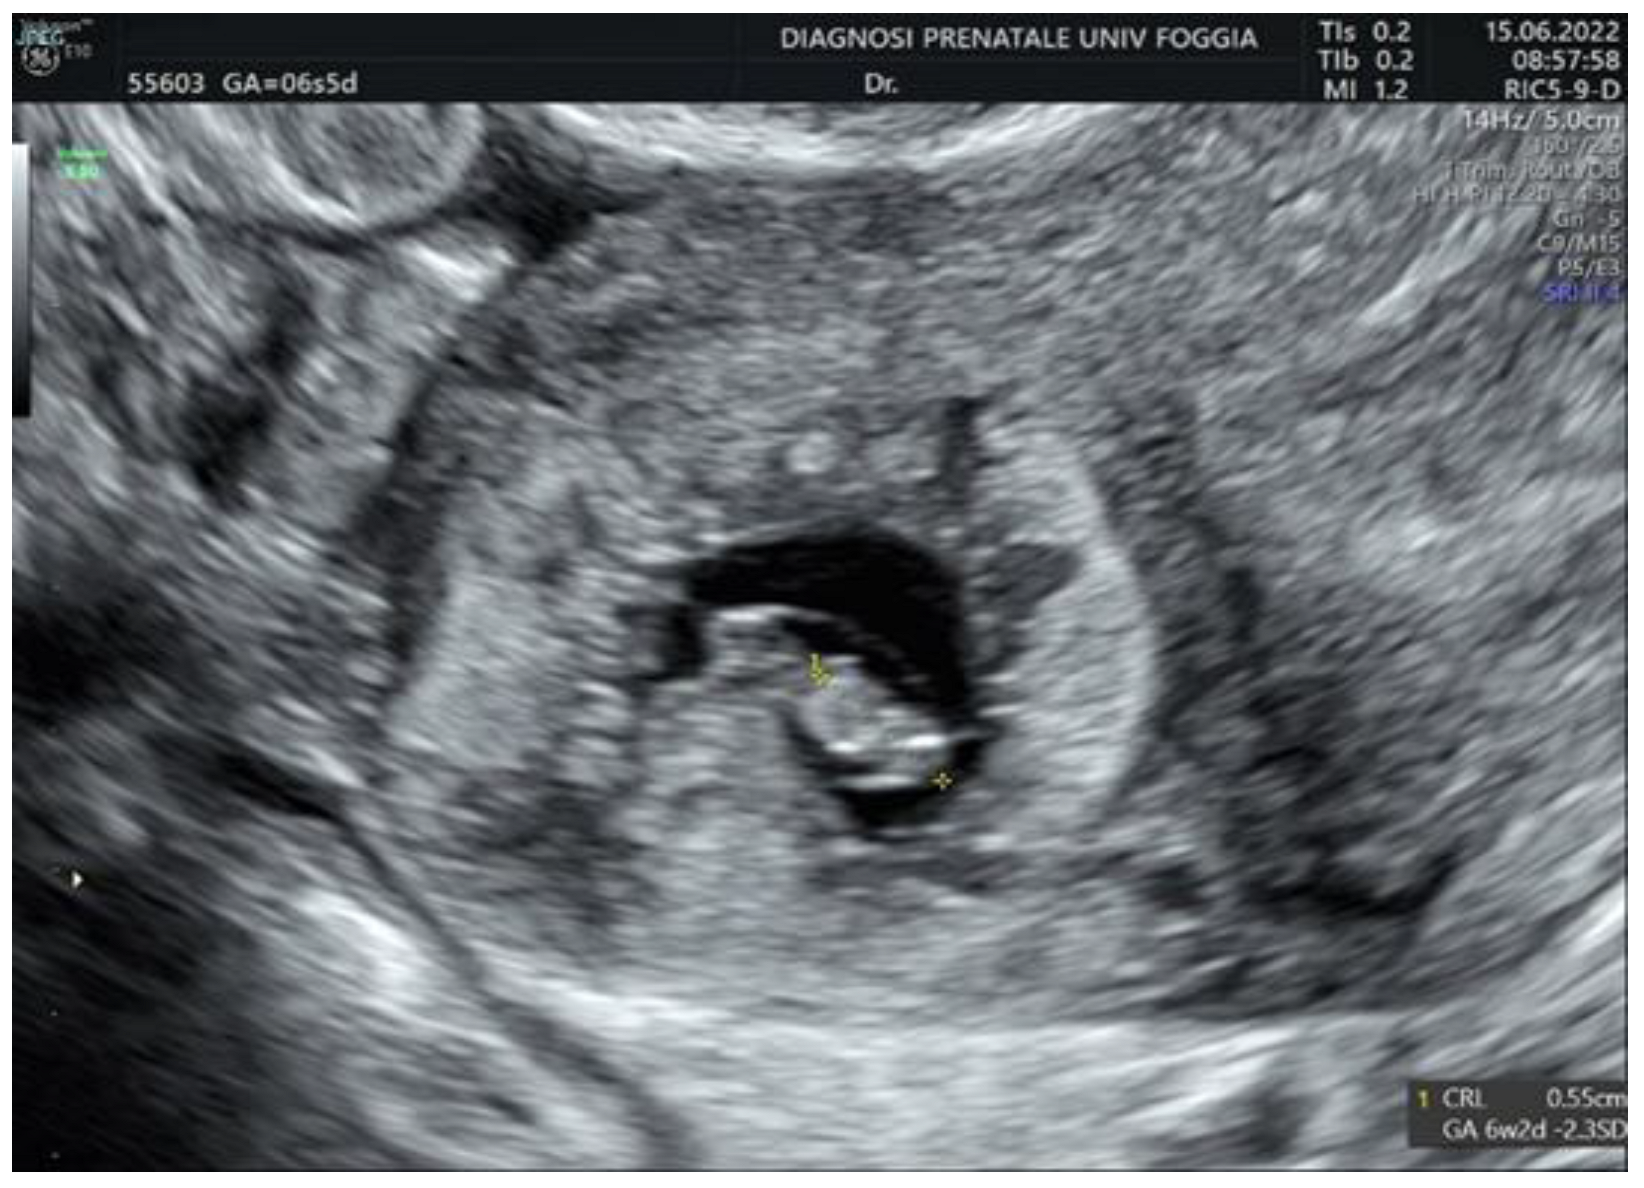

2. Case Presentation